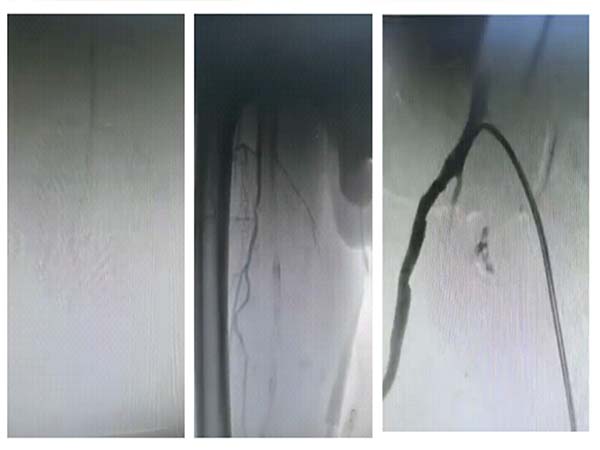

手术效果立竿见影。术后造影清晰显示,患者闭塞的下肢动脉彻底打通,血运恢复通畅,缺血症状当即缓解。术后患者下肢疼痛快速减轻,皮温明显回升,足背动脉搏动恢复,经后续治疗已能轻松行走数百米。